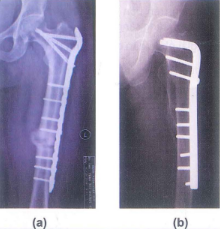

Hình 6.9. Gãy phức tạp khối mấu chuyển thân xương- phẫu thuật mổ mở sử dụng đinh nội tuỷ đầu trên xương đùi

Hình 6.9a: Nẹp đầu trên xương đùi với gãy phức tạp DMC và thân xương đùi sau 10 tháng

Hình 6.9b: Nép góc 95 độ điều trị gãy DMC, có ghép xương vào thành sau trong 1 năm

Hình 6.12. KHX nẹp vít đầu trên xương đùi (Medtronic) ít xâm lấn